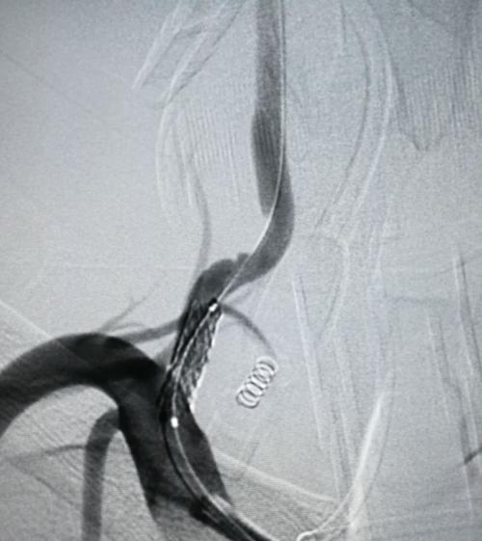

病例分享:

CEA同期颈动脉-椎动脉转流

患者信息:60岁男性,右手麻木无脉1年,伴高血压、糖尿病。

影像资料:右锁骨下动脉闭塞,右颈动脉狭窄,左椎动脉狭窄。

图:术前影像资料

手术方案:通过显露椎动脉、大隐静脉搭桥及同期CEA(术中三向转流),实现血运重建。